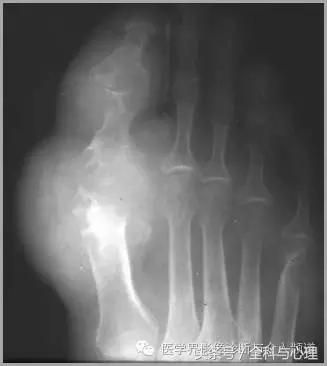

4、痛风石

为尿酸盐沉积形成,发生在关节周围软组织、包括韧带、肌腱、滑囊,眼、耳、鼻、喉、皮肤, 50%的钙化为X线平片可见。

痛风石,可见软组织肿胀及钙化灶。